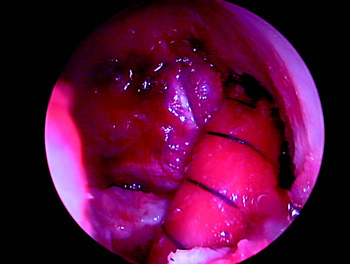

Creemos que el gran aporte de la cirugía con doble banda ha sido analizar el control rotacional, hecho que podemos lograr con una banda al reubicar la inserción femoral en un punto más a las 3 o a las 9 del reloj horario, existen muchas publicaciones que lo avalan (19, 20, 21). Musahl (22) muestra en su estudio que los túneles femorales dispuestos en forma más horizontal aportan mejor control rotacional. La tendencia actual es ubicar el túnel femoral más horizontal, remedando la huella de inserción del LCA, lo cual se puede lograr utilizando un portal anteromedial, que en nuestra experiencia utilizamos poco, como también medializando el túnel tibial y redirec-cionándolo con una dilatación mínimo de 2 mm (Fig. 1). Con esto logramos llegar de una forma más horizontal a la pared femoral obteniendo así un mejor control rotacional. (Figs. 2 y 3).

Figura 3: Colocación del injerto en posición anatómica de una banda única. |